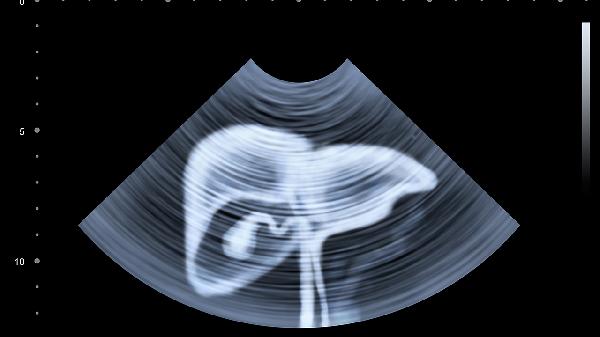

肝脏再生主要通过肝细胞增殖实现。当肝脏部分切除后,剩余肝细胞会迅速进入细胞周期,开始分裂和增殖。肝星状细胞和胆管细胞也参与这一过程,帮助重建肝脏结构和功能。再生过程中,肝脏会分泌多种生长因子和细胞因子,如肝细胞生长因子HGF和表皮生长因子EGF,这些物质促进细胞增殖和组织修复。